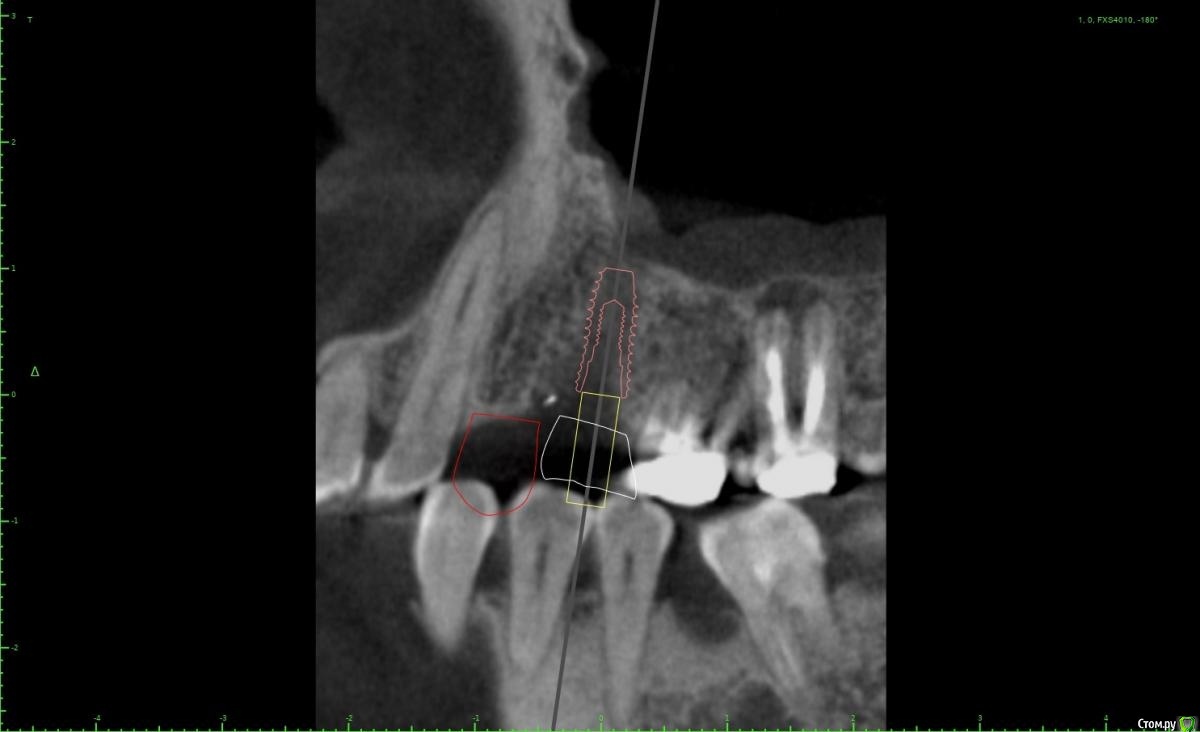

Женька Опубликовано 5 февраля, 2021 Автор Поделиться Опубликовано 5 февраля, 2021 Я бы развел винты побольше, лучше ближе к зубам чем друг к другу, кроме того дистальный имплант можно сместить немного небнеекак-то так? 1 Ссылка на комментарий

Irouil Опубликовано 5 февраля, 2021 Поделиться Опубликовано 5 февраля, 2021 Вроде того, 5ку можно еще немного небнее и ангуляцию вестибулярнее чтобы выход шахты оставить неизменным, смысл в том, чтобы пользоваться пространством возле небного корня 6ки. Ссылка на комментарий